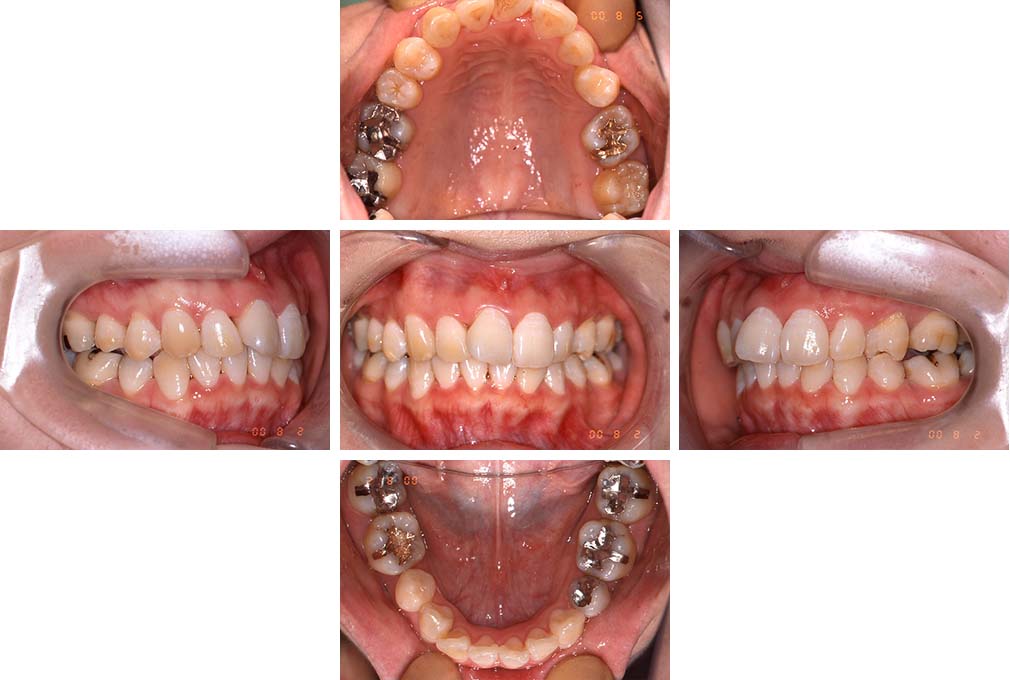

CASE:04

アングルⅢ級傾向を持つ叢生

初診時年齢 22歳

性別 女性

治療費の目安 105万円程度(治療開始時)

上顎右側犬歯が唇側に転位していることを主訴に県内歯科医院から紹介来院された。骨格的にはⅢ級傾向で上顎右側犬歯が唇側転位となり、側切歯が口蓋側に転位していた。下顎前歯が叢生になっていることも相まって上下の正中線は右側に大きくずれていた。アングルⅢ級傾向を持つ上下顎前歯部叢生と診断した。

上下顎小臼歯を抜歯していただき上顎舌側、下顎唇側マルチブラケット装置を使用して動的治療を行った。矯正用ゴムの使用など協力状態も良く、正中線の大きな移動があったのも関わらず2年10カ月で装置を撤去し保定へ移行した。保定移行後14年が経過し、ご息女の診察でご来院いただいていたことから、口腔内を拝見したが、下顎前歯のわずかなずれがあったものの大きな歯列の乱れはなく歯列は安定していた。動的治療期間2年10カ月間。

治療前

22歳6か月

治療後

動的治療期間2年10カ月間

25歳6か月

治療終了

動的治療終了後2年2カ月

28歳8か月

14年経過

動的治療終了後14年7カ月

40歳1か月